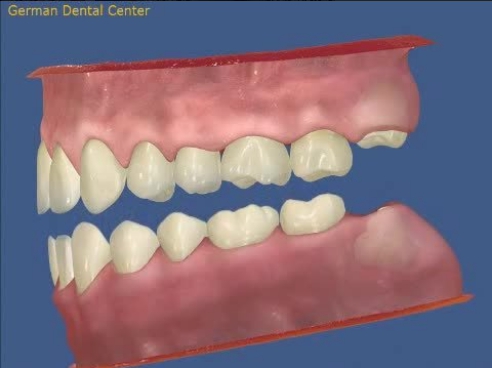

- Исправление прикуса

- Протезирование